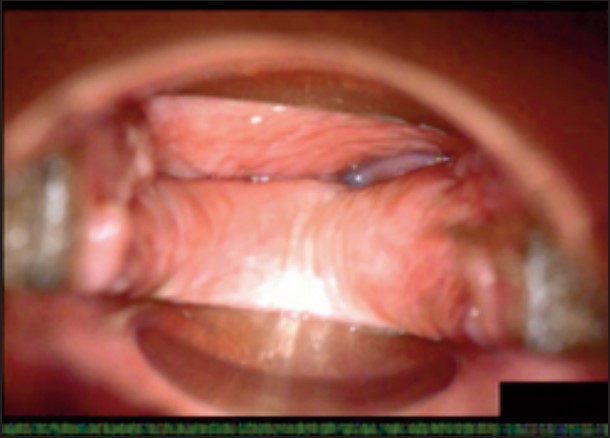

У пацієнток 1, 2 і 3 вагінальні складки утворилися та увиразнилися помітніше та сильніше, ніж вони були до лікування, ми оцінили цей клінічний результат після 1-го сеансу (через 16 діб). На нашу думку, такі виразні складки свідчать про підтяжку слизової оболонки піхви, що добре впливає на ущільнення піхви та проблему нетримання сечі. Через 36 діб після процедури ми спостерігали, що зруйнована анатомічна структура піхви відновила Н-подібну форму, тобто стала набагато здоровішою. Зокрема, у пацієнтки 4 структура піхви була цілковито зруйнована, стінки піхви обвисали через втрату еластичності. Однак через 36 днів після процедури структура піхви повністю відновила здорову Н-подібну форму [Див. Малюнок 3].

Пацієнтка №3

Після 16 діб

Після 36 діб

| Вік | 46 |

| Пологи | Природні. 2 хлопчики. |

| Лікування | 2 сеанси / 1 місяць |

| Огляд | 16, 36 діб |

| Протокол | 1 сеанс – 440 імпульсів 2 сеанс – 200 імпульсів |

| Результати | √ Відновлено H-подібну структуру √ Дещо зменшилися симптоми SUI √ Зросло задовлення партнера √ Зросло задоволення пацієнтки |